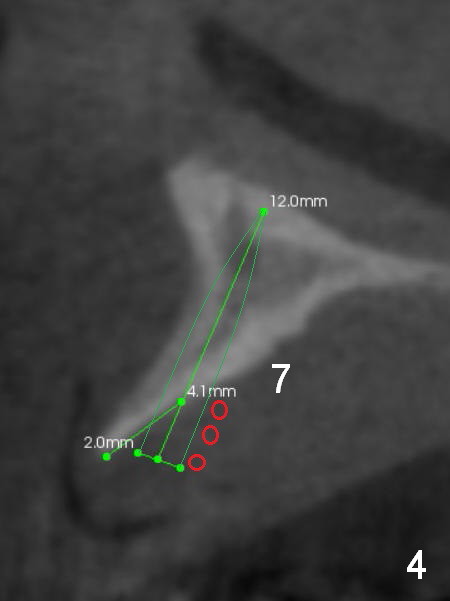

A 69-year-old man would consider implant option for his upper front teeth (Fig.1: #5-9) if there is no separate bone graft procedure. He does not want implants for his lower left molars (#18,19), since he has had a partial denture. In fact the bone at #5-9 is so thin that 2-3 mm 1-piece implants can be placed at #5,7 and 9 (Fig.2-5 (CT coronal sections (B: buccal)) for a 5-unit bridge (Fig.1). To support and increase the longevity of the latter, implants at #18,19 are mandatory (Fig.6,7).

Wheel saws will be used to split the ridge before drilling at #7 (Fig.4). Surgical bur is to be used for ridge reduction prior to osteotomy at #19 (Fig.6), while at #18, osteotomy depth will be 10 mm for 8 mm implant (Fig.7).